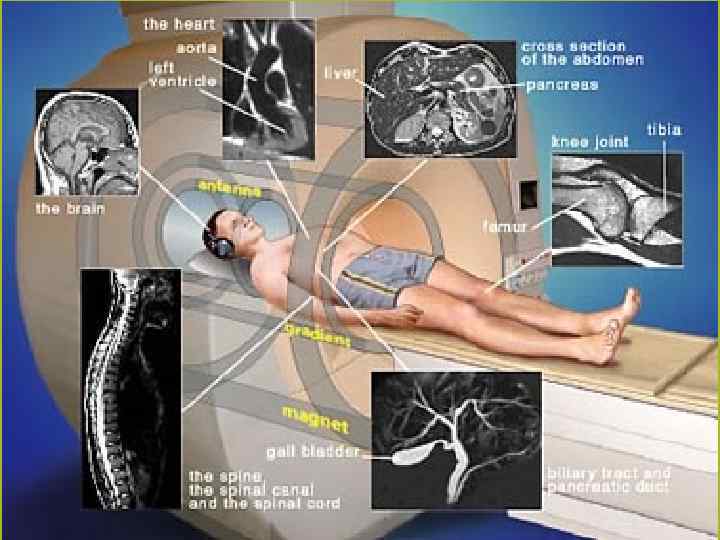

МАГНИТНО-РЕЗОНАНСНАЯ ТОМОГРАФИЯ(МРТ) СЕРДЦА Магниттi - резонанстық томография орталық жүйке жүйесi, омыртқаның ауруларын диагностика арқылы зерттеудiң аналог болмайтын сирек кездесетiн iс жүзiнде бұлшық еттiк болып табылады - буын жүйе және iшкi органдардың қатары. Сутектiң протондарын адамның организмінде резонанста негiзделгеннiң зерттеу онының магниттi алаңына үй-жайда. Сәулелiк жүктеменiң жоқтығы емделушi үшiн магниттi - резонанстық томография қауiпсiз iстейдi және бiрнеше тексерулер қатар өткiзуге мүмкiндiк бередi

Жағдайларды қатарда көк тамырiшiлiк қарама-қарсы күшейтуi бар зерттеудiң өткiзу МРТ диагностикалық қажеттiлiгi пайда болады. Зерттеудiң мәлiметтерi дәрiгер МРТ емдеушi дәрiгер немесе бағыт бойымен тек қана жүргiзiледi. Қарама-қарсы препараттың енгiзуi қосымша реакциялардың ең төменгi тәуекелiнде болады. Сiзгеге контрасты заттың енгiзуi жағдайда сауалнаманы толтыруға ұсыныс жасайды - қарама-қарсы препараттың көктамырiшiлiк енгiзуiне ақпараттық келiсiмнiң парағы.

Зерттеуге абсолюттiк қарсы көрсетулермен жатады: ми ыдыстарында кардиостимулятордың бар болуы, ферромагниттi имплантовтары, клипс. Зерттеу бұл жағдайдалардағы қатал қарсы көрсеткен. (зерттеу өткiр қажеттiлiктiң жанында жүргiзiле алады) салыстырмалы қарсы көрсетулерге металлдың мазмұнымен жүктiлiктiң бiрiншi триместрi, жүректiң жасанды клапандары, орнын толтырмалған жүрек мүкiсi, инсулин сорғылары, импланты, металлдық брекетыларда әкетедi. Сонымен бiрге темiрi бар бояуларды қолданумен салыстырмалы қарсы көрсетулер сияқты қарау керек болуға iстеп шығылған татуировкалар.